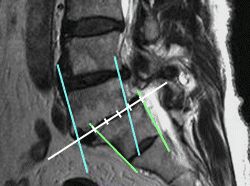

腰の骨すべり症 25%

腰の骨5番が、25%(1/4)前方にすべっているのが見られます。

その位置で脊髄神経が折れ曲がっているのが分かります。